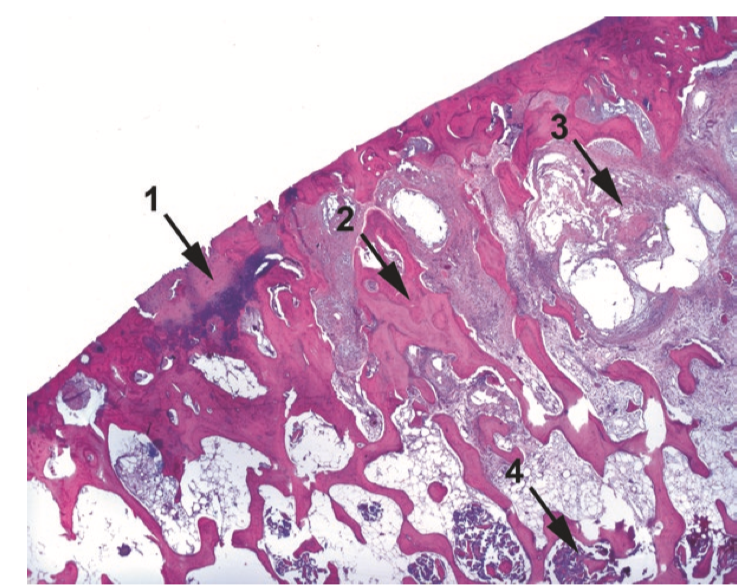

Osteoarthritis. Features include (1) eroded cartilage, in this case nearly absent, and irregular mineralization of the cartilage, seen here as a dark purple stain; (2) thickening of the subchondral bony trabeculae; (3) myxoid degeneration of the subchondral bone, forming cyst-like spaces; and (4) some residual hematopoietic marrow.